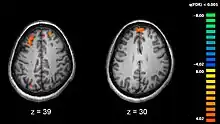

The areas most actively involved in episodic encoding and retrieval are the medial temporal lobe (hippocampus) and the prefrontal lobe.

Associated neural activity

Recent research using neuro-imaging technology including PET and fMRI scanning has shown that there is an extensive amount of distributed brain activation during the process of episodic encoding and retrieval. Among the various regions, the two most active areas during the constructive processes are the medial temporal lobe (including the hippocampus) and the prefrontal cortex.[15] The Medial Temporal lobe is especially vital for encoding novel events in episodic networks, with the Hippocampus acting as one of the central locations that acts to both combine and later separate the various features of an event.[16][17] Most popular research holds that the Hippocampus becomes less important in long term memory functioning after more extensive consolidation of the distinct features present at the time of episode encoding has occurred. In this way long term episodic functioning moves away from the CA3 region of the Hippocampal formation into the neocortex, effectively freeing up the CA3 area for more initial processing.[17] Studies have also consistently linked the activity of the Prefrontal Cortex, especially that which occurs in the right hemisphere, to the process of retrieval.[18] The Prefrontal cortex appears to be utilized for executive functioning primarily for directing the focus of attention during retrieval processing, as well as for setting the appropriate criterion required to find the desired target memory.[15]